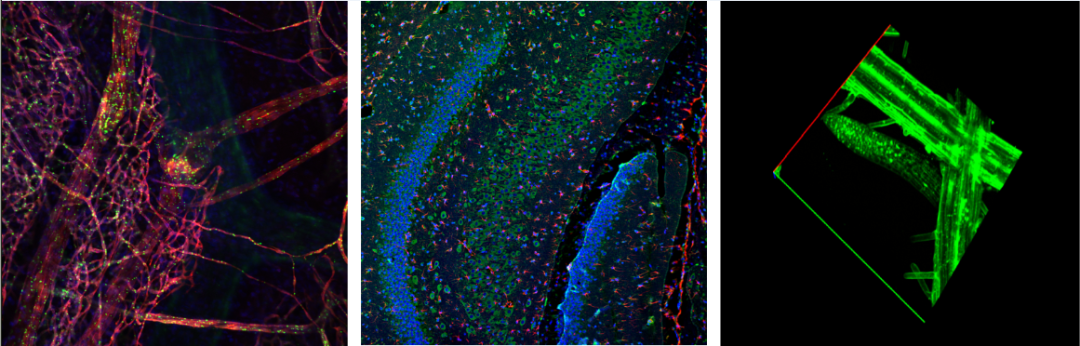

四川華西醫院斑馬魚骨架染色分析,利用Z序列掃描功能可實現1um步進設置下297張Z軸圖像的采取,清晰還原斑馬魚頭部骨架形態完成空間結構觀察。

華中科技大學腸系膜共定位分析,配置Nomis Advance共聚焦分析軟件可實現不同熒光標記蛋白在同一區域上的分析判斷,自研邏輯算法保證圖像數據獲取準確、定量分析快速方便,精簡實驗研究過程。

山東大學生命科學院擬南芥根尖的GFP表達,NCF950采用六邊形電動針孔設計,電動控制成像實現穩定、快速、高信噪比的圖像觀察,Z序列層掃功能有助于根尖信號的逐層定量分析完成實驗目的。